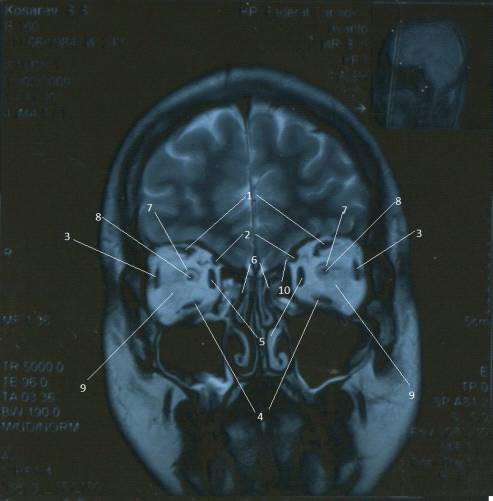

Проекция МРТ №6

На Проекции МРТ №6

визуализируются следующие анатомические

образования:

1.Глазное яблоко - Bulbus

occuli

.Верхнее веко - Palpebra

superior

.Блок - Trochlea

. Верхняя косая мышца - M.obliquus

. Твердая оболочка зрительного нерва

.Зрительный нерв - N.

opticus

. Латеральная прямая мышца - M.

Rectus lateralis

. Ретробульбарное пространство - Spatium

retrobulbar